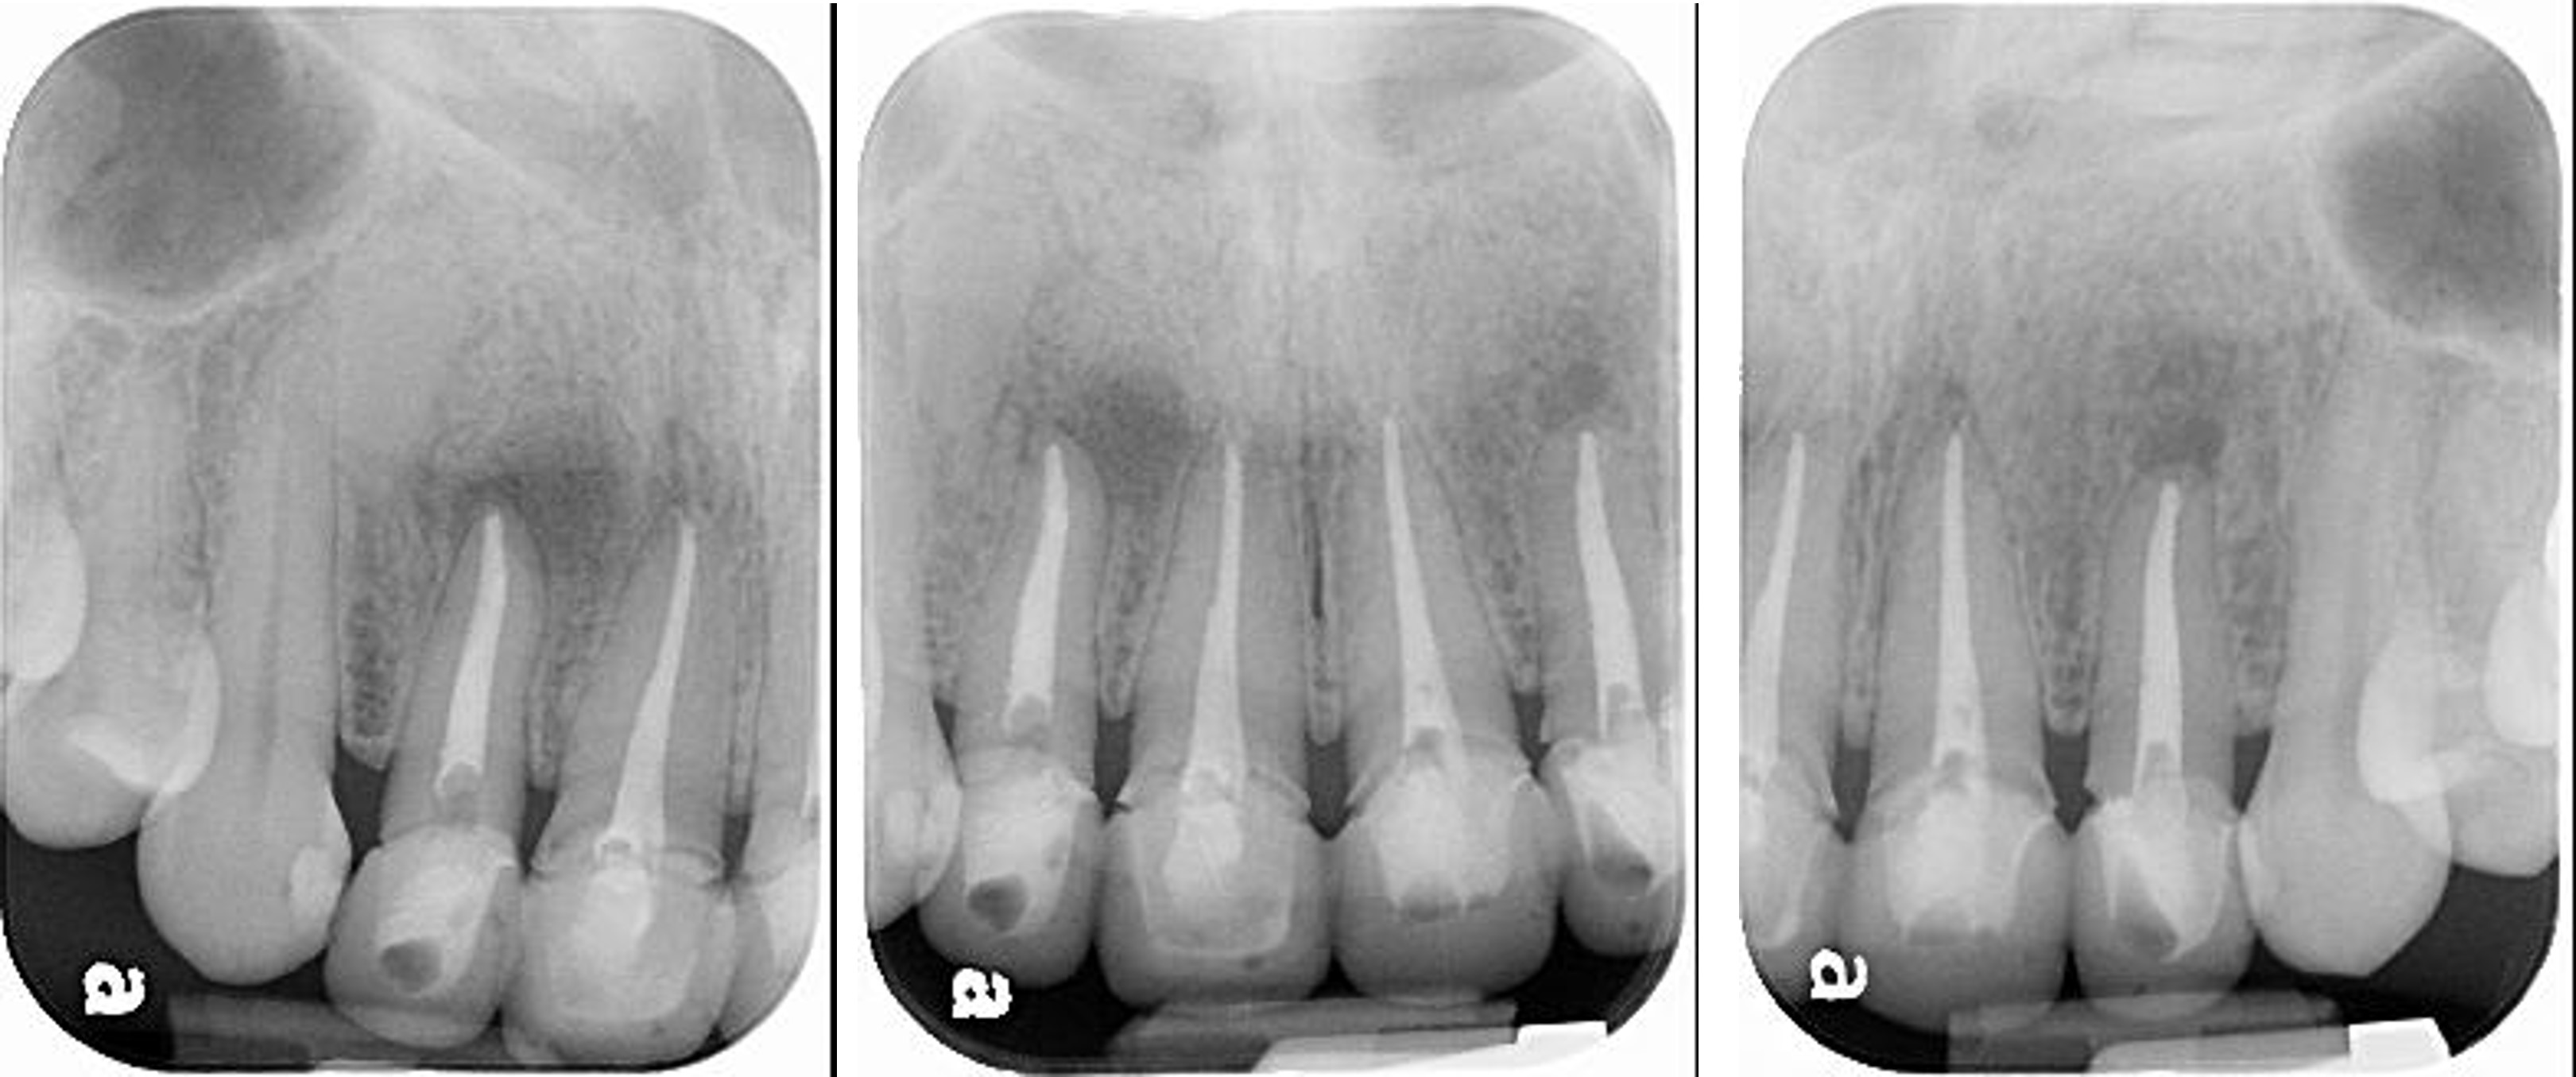

上顎前牙有瘻管,牙齒變色,右下有阻生齒與蛀牙

治療前,前牙病變,阻生齒等

治療前,前牙根管治療不完全

根管治療6個月後,仍有根尖病變

6個月後病變逐漸恢復

再6個月後,病變更消失